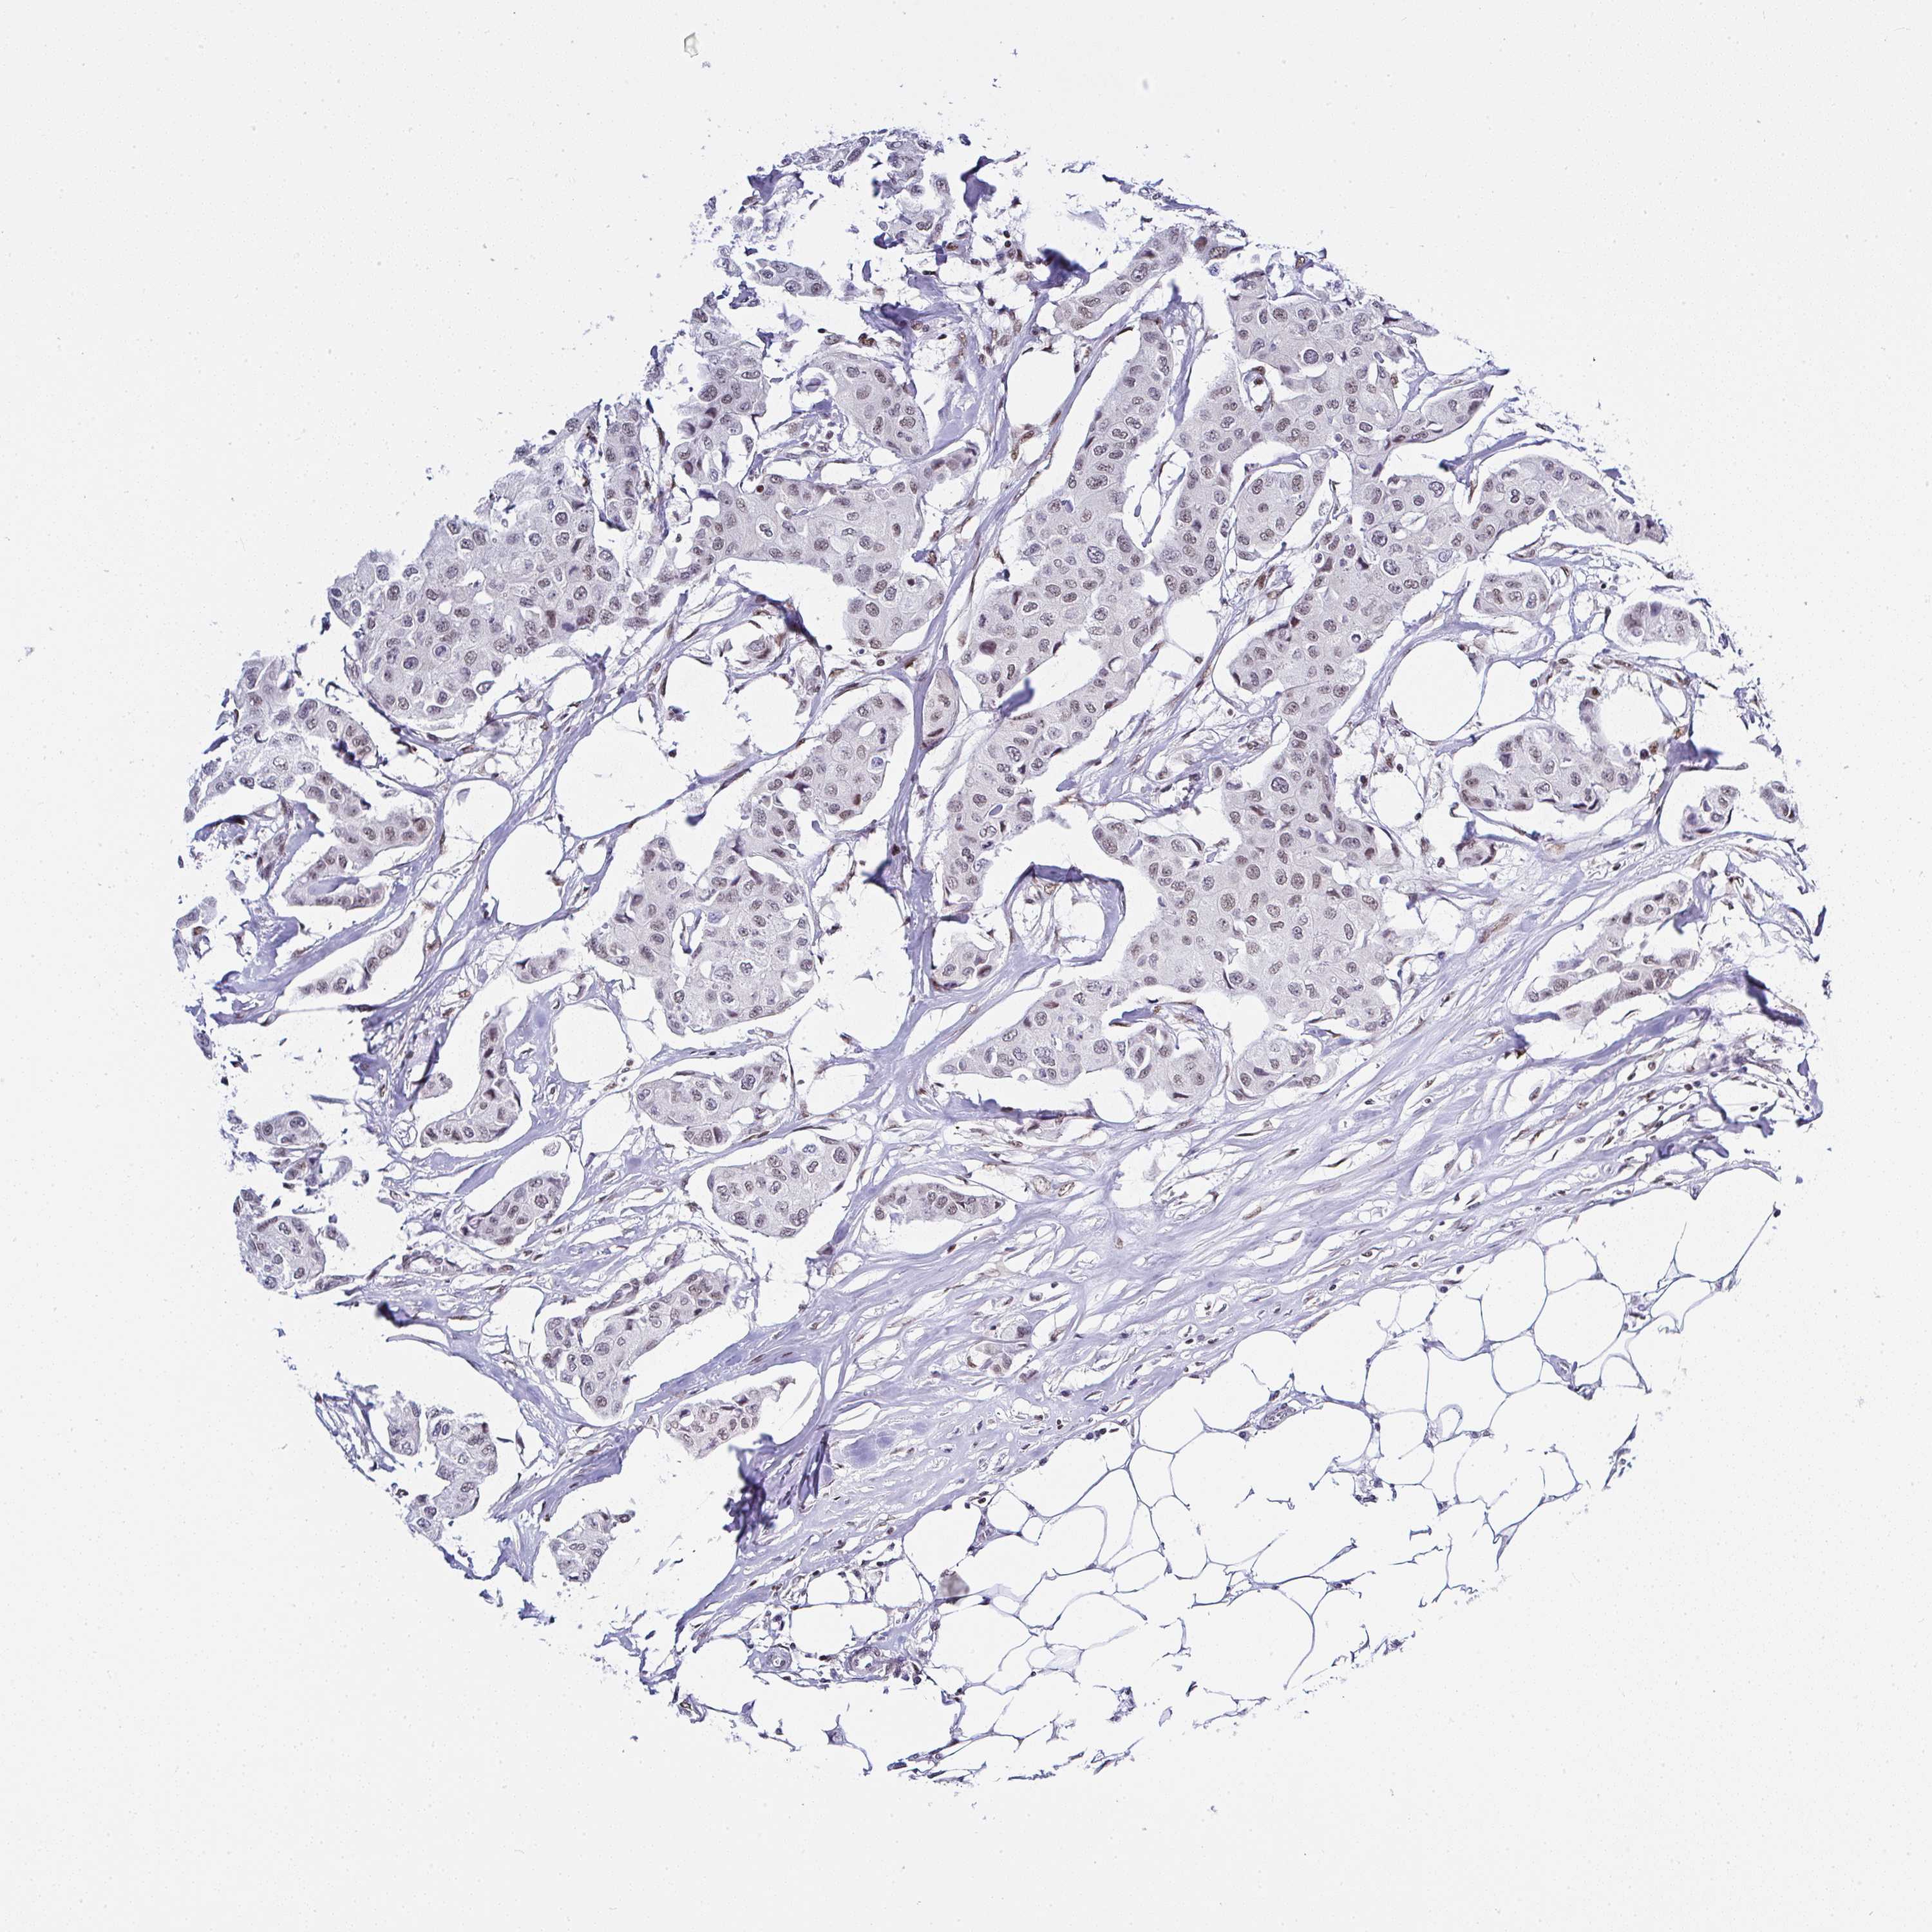

BRCA TCGA BRCA VALIDATION PROTEIN EXPRESSION

ANTIBODIES

AND

VALIDATION